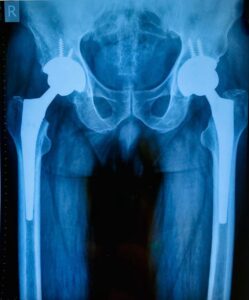

Hip replacement surgery involves removing the damaged hip joint and replacing it with a prosthetic. There are two main types:

- Total Hip Replacement (THR): Both the hip socket and the ball of the femur are replaced with artificial components.

- Partial Hip Replacement: Only the ball (femoral head) is replaced if the socket remains intact.